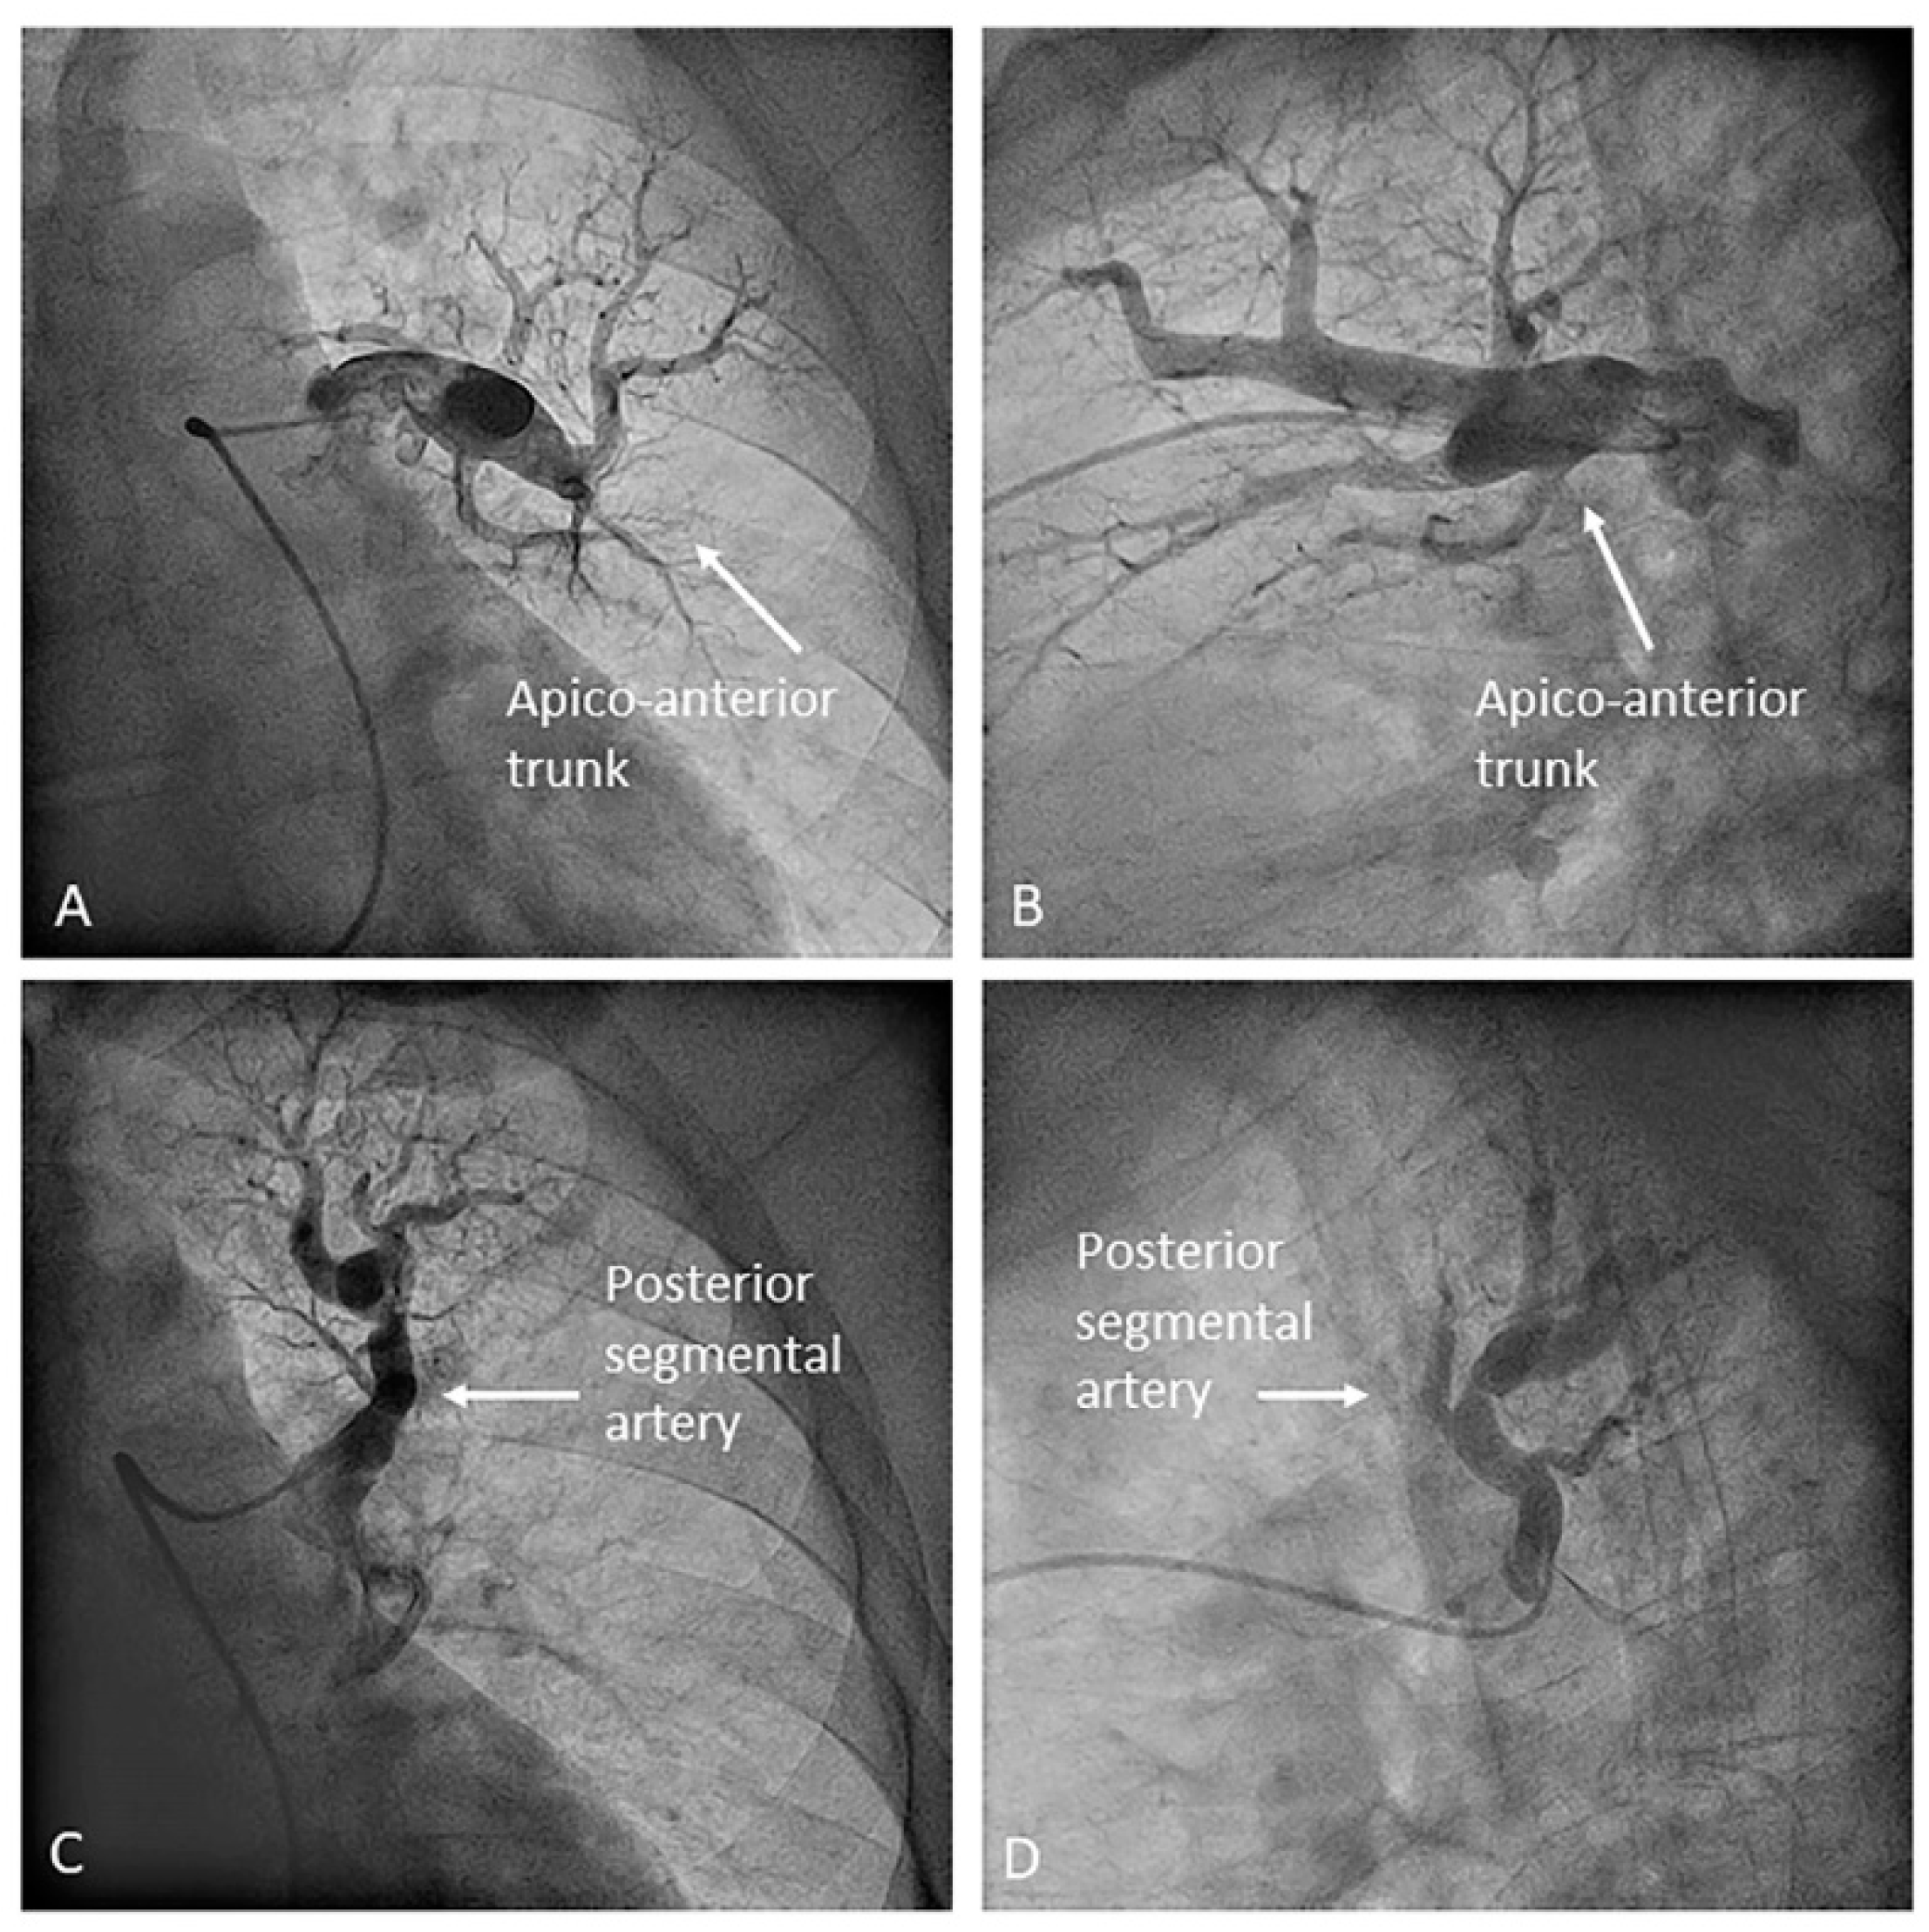

- Left upper lobe. The apico-posterior trunk (A1/2) is easily cannulated in the AP view. We should rotate the MP-A2 catheter counterclockwise in the proximal segment of the LPA to make the tip face upwards (Figure 23). The apical and posterior segmental arteries (A1 and A2) are well visualized by filming in the AP and lateral views. The anterior segmental artery (A3) is engaged more easily with the Judkins left catheter (JL) 3.5 or 4. Position the JL below the aortic arc in the AP view with the distal tip facing the left lateral chest wall. Rotate the catheter counterclockwise and withdraw it slightly. The distal tip of the catheter will climb 2–3 cm, engaging the anterior segmental branch (A3) (Figure 24). Film this branch in the cranial RAO and lateral views.

- Right upper lobe. The right upper lobar artery arises about 10 cm from the bifurcation. It is cannulated in the AP view with the tip of the MP-A2 facing upwards. The apico-posterior segmental artery (A1/2) is canalized just by advancing the MP distally once in the right upper lobe artery. The AP and lateral views display the apical (A1) and posterior branches (A2) (Figure 28). The anterior segmental artery (A3) is canalized in the lateral view, rotating the MP counterclockwise from its position in the apico-posterior artery (A1/2). With this maneuver, the tip of the catheter moves downwards, facing the sternum and engaging the anterior segmental artery (A3) (Figure 29). This branch should be filmed in lateral and cranial AP/cranial LAO view.